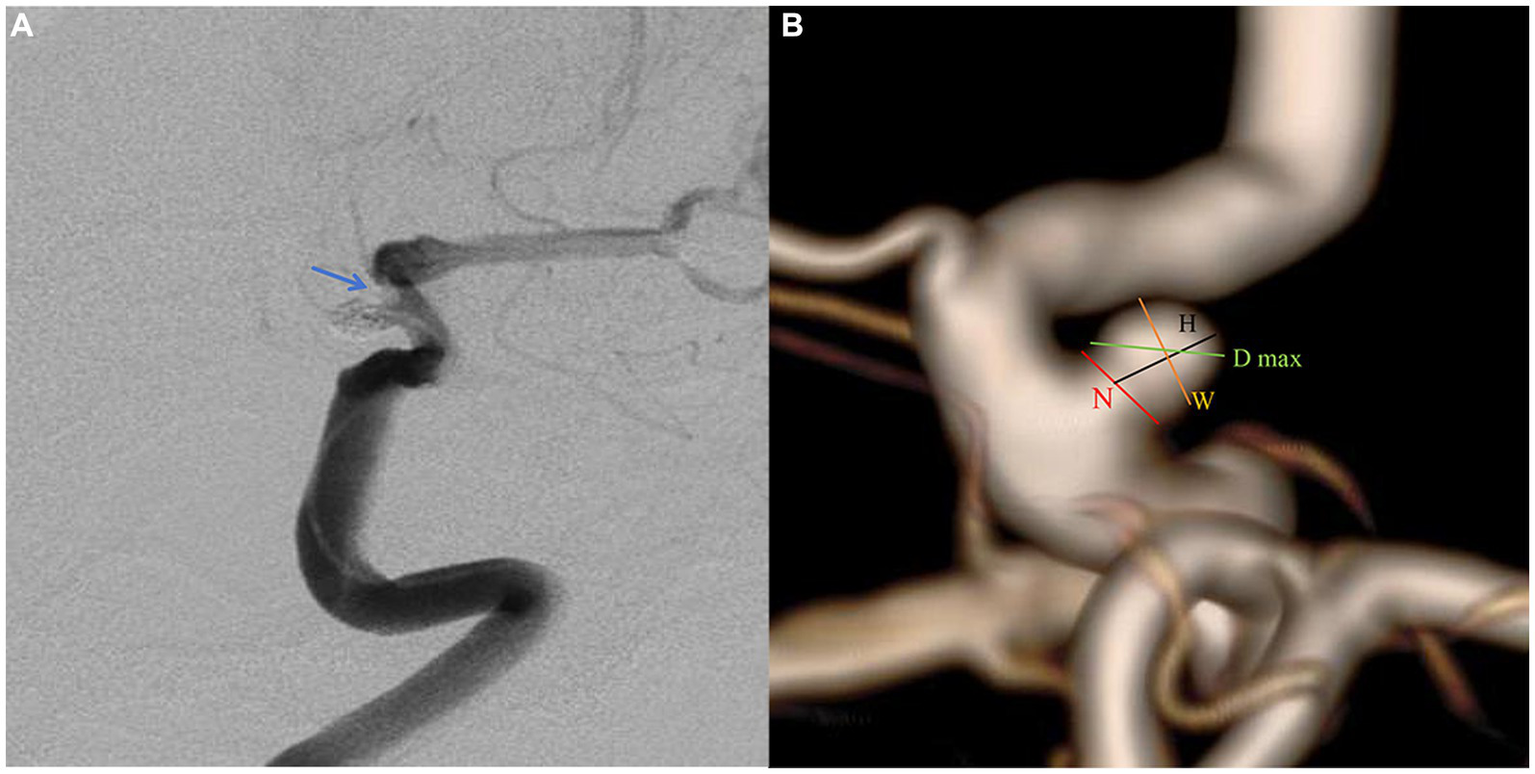

The patient selection flowchart is presented in Figure 1. The study received approval from our hospital’s institutional ethics committee, and we collected data after obtaining informed consent from the patients or their close relatives. From May 2021 to September 2022, 489 patients with unruptured PAs via digital subtraction angiography (DSA), and 172 underwent SAC. 317 patients were excluded for the following reasons: (a) FD treatment (n = 294); (b) refusal to undergo surgery (n = 8); (b) coiling alone (n = 7); (c) fusiform or dissecting aneurysm (n = 4); and (d) prior treatment history (n = 4). The 172 patients were divided into an IST group (n = 12) and a non-IST group (n = 160). The diagnostic criteria for IST included intraoperative DSA demonstrating contrast agent filling defects or delayed blood flow in the parent artery (Figure 2A).

Figure 2

A paraclniod aneurysm of two-dimension and three-dimension digital subtraction angiography (DSA). (A) Two-dimension DSA showing the in-stent thrombosis (blue arrow). (B) The definition of morphologic variables in three-dimension DSA.

Pretreatment DSA images and three-dimensional reconstructions were obtained for each patient using the Innova Workplace system (GE Medical). Two experienced neuro-interventional surgeons performed measurements of morphological parameters using the same procedure, and we defined the parameters as the average of their values. The results were precise to two decimal places. The morphologic variables were defined as follows (Figure 2B):

Maximum diameter (D max): The aneurysm’s maximum diameter.

Height (H): The maximum distance from the center of the aneurysm neck to a point on the sac.

Width (W): The maximum distance perpendicular to H.

Neck diameter (N): The maximum diameter in the neck plane.

Size ratio (SR): The ratio of H to the Parent artery diameter.